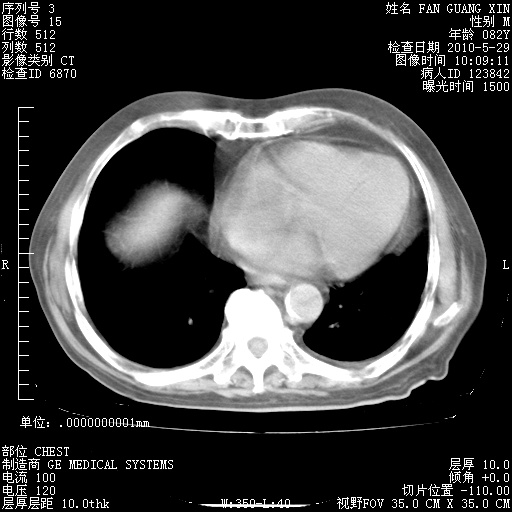

再治疗10天后的肺部CT 纵膈窗

阅读此次胸部CT,肺间质渗出性改变较入院时有吸收。目前从体温、白细胞、中性分叶明显增高,肯定存在细菌感染(发生医院感染哦,若无消化道及泌尿系统等感染的依据,肺部感染可能大)。若你院头孢哌酮舒巴坦钠耐药率较高,同意你的方案,若48小时体温仍高,可考虑使用碳青霉稀类抗菌药物,同时可予超声雾化、注意滴数时加大液体量。白蛋白33.30g/L较低哦,需加强营养等支持治疗。